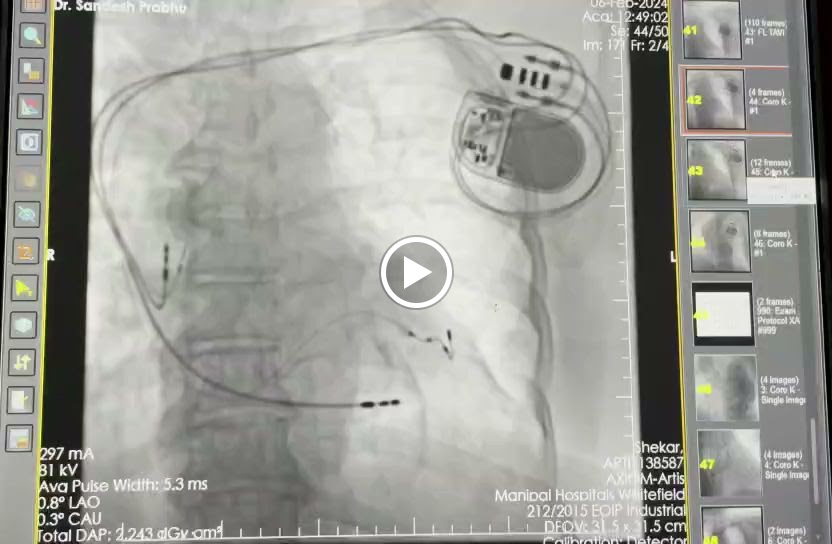

Videos